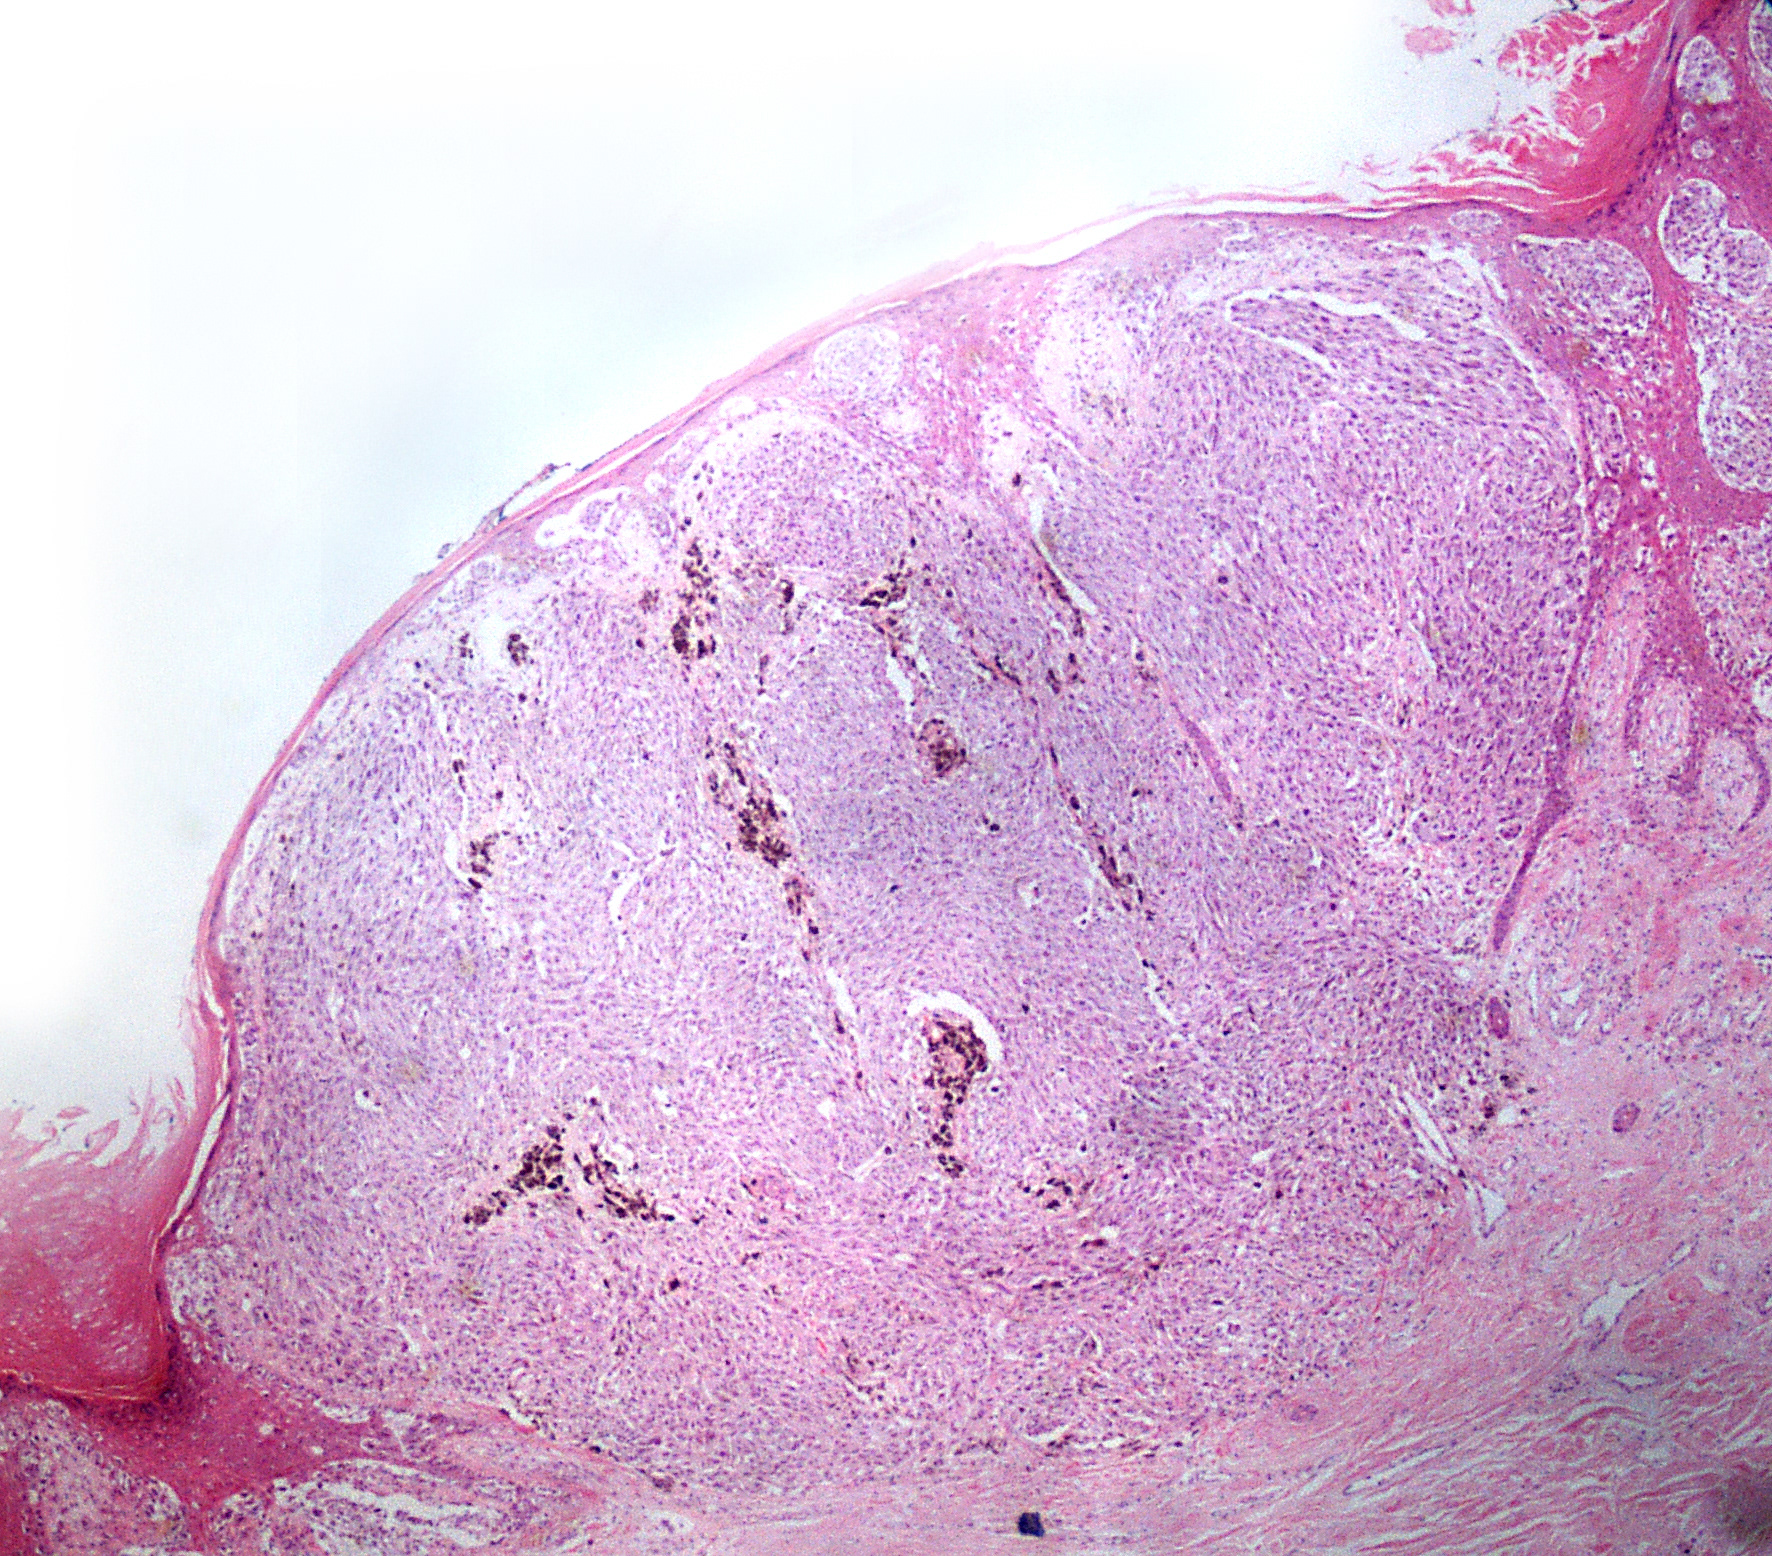

MELANOMA

These two images below show a cutaneous melanoma in what is known as a vertical growth phase. Not all melanomas in the body produce melanin pigment but within the tumour shown here brown pigment can be easily identified. This irregular production of pigment gives rise to the asymmetry and colour variation that can be seen when examining abnormal moles with the naked eye.